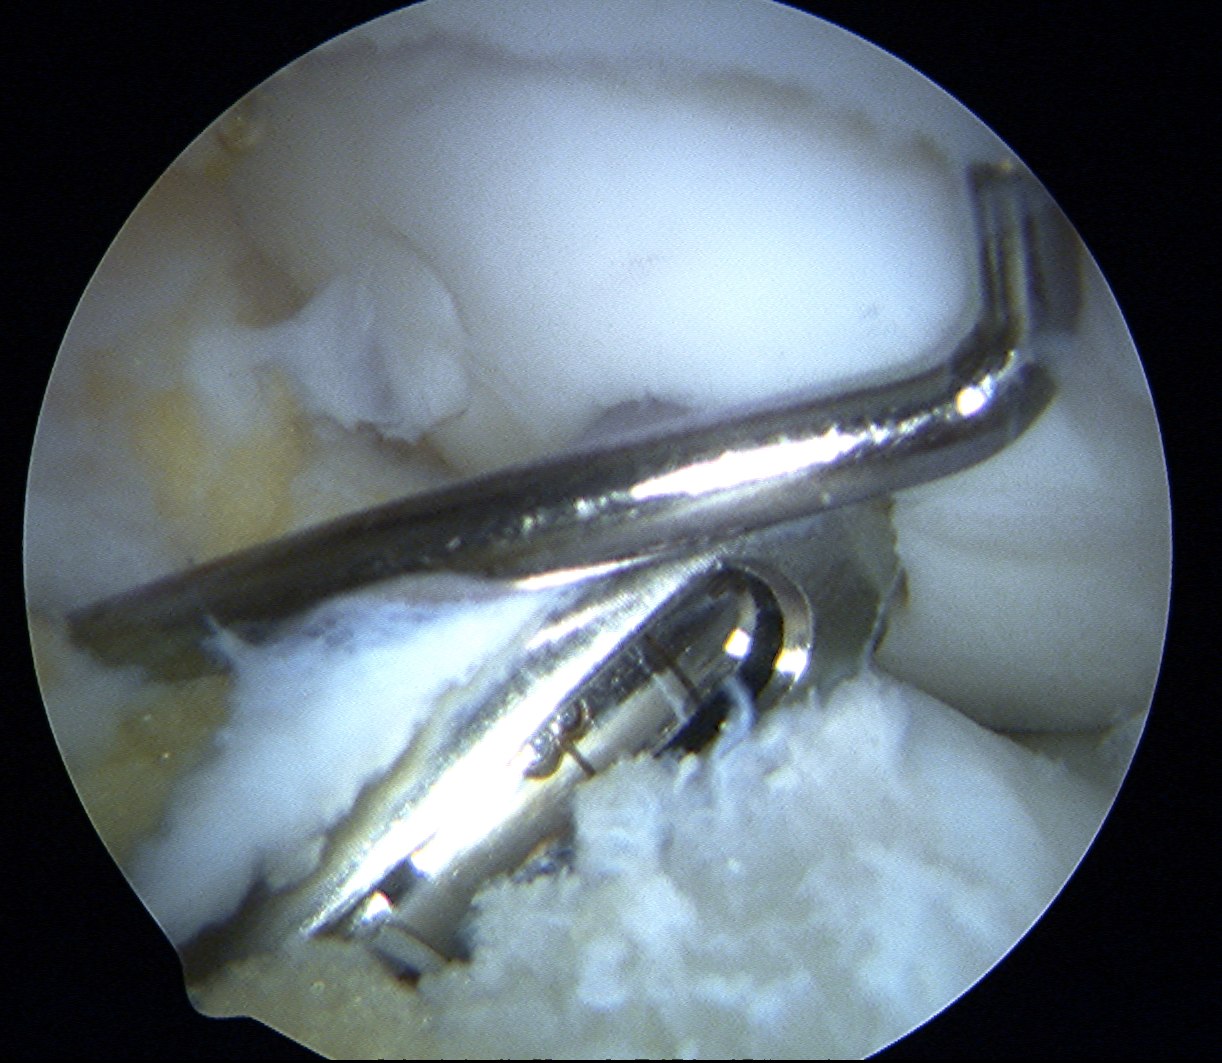

Insert dilator

Insertion device

- place over drill hole

- impact with hammer to seat in cartilage

- insert plug

- use tap to insert plug

- best to countersink 1 - 2 mm